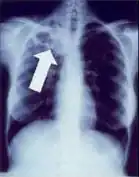

Radiografia ao peito de uma pessoa com tuberculose avançada. As setas brancas assinalam a infeção em ambos os pulmões. As setas pretas assinalam a formação de uma cavidade.

A tuberculose cria cavidades visíveis em radiografias como esta, na parte superior do pulmão direito.

Uma radiografia postero-anterior do tórax é a tradicionalmente feita; outras vistas (lateral ou lordótico) ou imagens de tomografia computadorizada podem ser necessárias.

Em tuberculose pulmonar ativa, infiltrações ou consolidações e/ou cavidades são frequentemente vistas na parte superior dos pulmões com ou sem linfadenopatia (doença nos nódulos linfáticos) mediastinal ou hilar. No entanto, lesões podem aparecer em qualquer lugar nos pulmões. Em pessoas com HIV e outras imunossupressões, qualquer anormalidade pode indicar a tuberculose, ou o raio-x dos pulmões pode até mesmo parecer inteiramente normal.